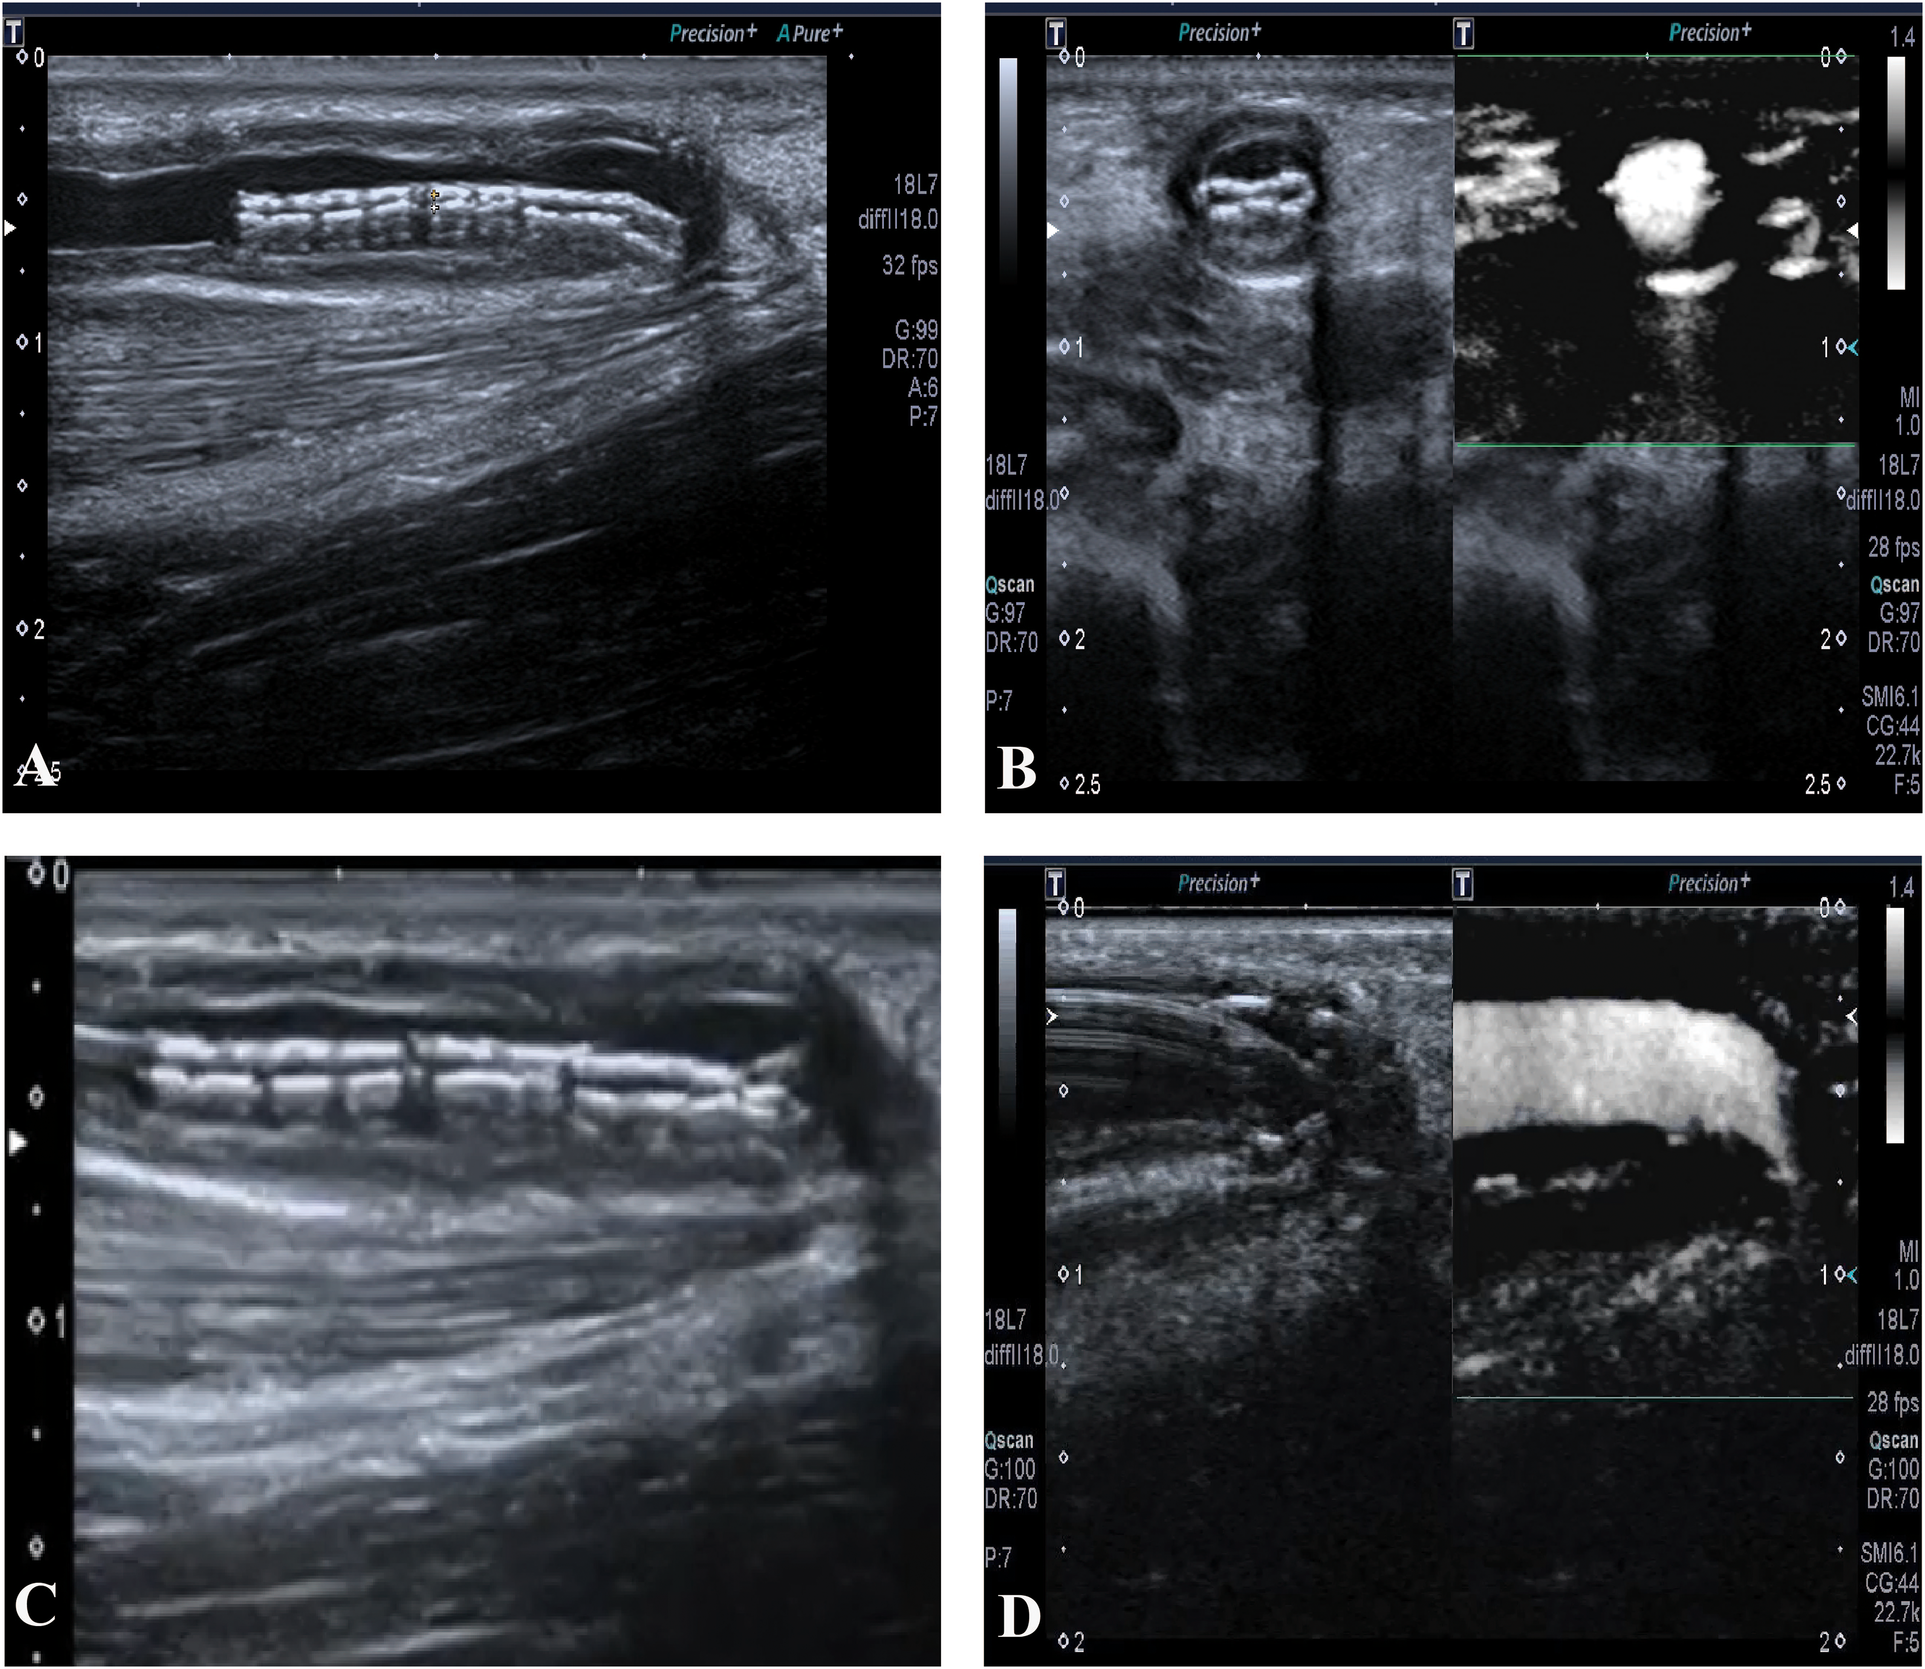

The right forearm AVF was patent for hemodialysis until the stent collapsed on 27 July 2018, with a primary patent duration of 14 months. No other postoperative complications occurred before the stent collapsed, such as thrombosis, heart failure, pseudoaneurysm, infection, or hemodialysis access-induced distal ischemia syndrome. Though the flow volume was acceptable, we still decided to expand the stent using PTA (Figure 2). On 30 July 2019, another restenosis occurred in the proximal part of the outflow vein of the right forearm AVF and was treated using ultrasound-guided PTA. On 26 December 2019, a thrombosis related to the restenosis in the proximal part was found by ultrasonography. Hence, the right forearm AVF was discarded. Instead, an arteriovenous graft (AVG) in the left forearm was constructed for maintenance hemodialysis since then, with one PTA procedure annually on average up to now.

Figure 2

(A) The collapsed stent in long-axis view. (B) The collapsed stent in short-axis view, with acceptable blood flow. (C) The guide wire advances through the collapsed stent. (D) The expansion of the collapsed stent using percutaneous transluminal angioplasty.